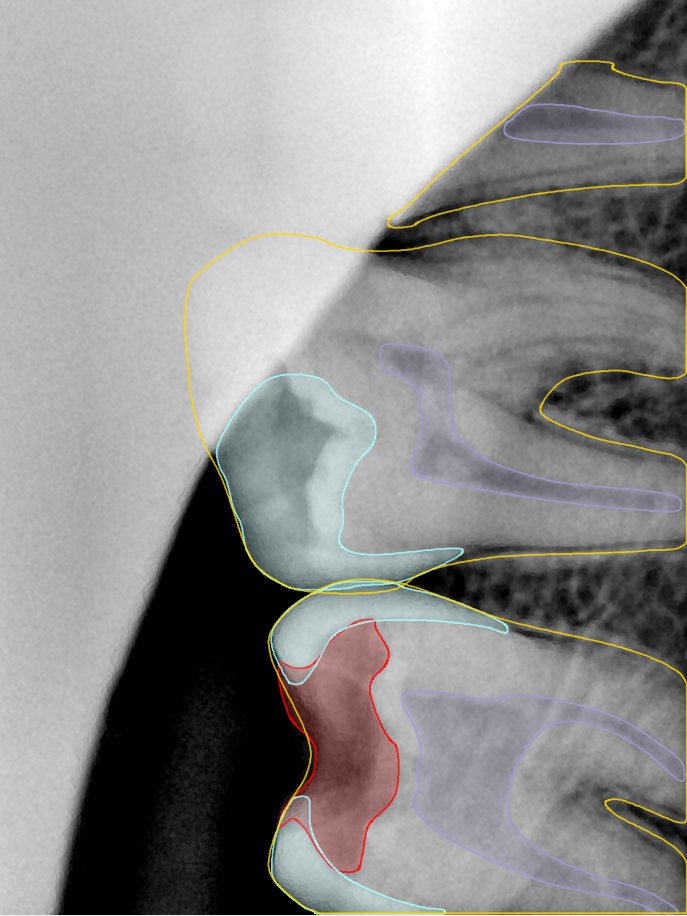

CR/DR 牙齿分割阶段记录

当前进展

- 完成了 CR/DR 牙齿相关分割训练

- 当前结果已经达到阶段预期,但仍有细节问题需要继续处理

相关测试

遇到的问题

- 训练过程中出现过 mask 下移问题

- 部分结果会出现 box 填充异常

- mask 边缘仍然有比较明显的锯齿感

参考

第二版算法问题测试

Updated: 2026-04-13(更新日期)

| 第一版 | 第二版 | 是否解决 | |

|---|---|---|---|

![]() | ![]() ![]() 边角识别有问题 龋齿识别不全 牙髓识别不全 | ![]() | 解决 |

![]() | ![]() 边角识别有问题 识别信息有误 自查(牙冠识别不全) | ![]() | 解决 |

![]() | ![]() ![]() 边角识别有误 大范围填充识别遗漏 | ![]() | 解决 |

![]() | ![]() 识别信息不全 | ![]() | 解决 |

![]() | ![]() ![]() 边角问题 牙胶识别不全 牙冠识别不全 | ![]() | 解决 |

![]() 换图片 | ![]() | ![]() 牙冠部分稍微白了一些就识别成小范围修补,部分判断异常 | 部分解决,修复类略敏感,牙冠部分稍微白了一些就识别成小范围修补,部分判断异常。 |

![]() | ![]() ![]() 牙冠识别不全 牙髓不全 根尖炎龋齿识别有误 | ![]() | 解决 |

![]() | ![]() | ![]() | 解决 |

![]() 换图片 | ![]() | ![]() | 解决 |

![]() | ![]() 牙冠识别有误 | ![]() | 解决 |

![]() 换图片 | ![]() ![]() 边角识别有误 | ![]() 修复类敏感 | 部分解决,图像过白,导致修复类判断异常。 |

![]() 换图片 | ![]() 牙冠识别不全 | ![]() 修复类敏感 | 部分解决,图像过白,导致修复类判断异常 |

结论:修复类出现了不鲁棒的情况,后续需要加入轮廓的扩充数据进行增强。